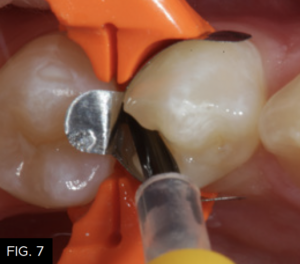

It is then rinsed off for a minimum of 15 to 20 seconds to ensure complete removal. The preparation is then air-dried and rewetted with G5 Desensitizer (Clinician’s Choice) to disinfect the cavity surface, create a moist surface for bonding, and begin initial penetration of HEMA into the dentinal tubules. A total-etch bonding agent (MPa Max, Clinician’s Choice) is then placed on all cavity surfaces. (FIG. 7) Chlorhexidine (0.2%) is included in MPa Max and will help inhibit the release of MMP’s (matrix metalloproteinases) from etched collagen that have been shown to weaken the dentin bond over time5. The solvent is evaporated by spraying a gentle stream of air across the surface of the preparation, while the adhesive is thinned until no rippling is seen. The adhesive is then light-cured for 20 seconds (Valo Grand, Ultradent). (FIG. 8)

The bonding resin (MPa Max, Clinician’s Choice) is placed using a microbrush on all etched enamel and dentin surfaces.